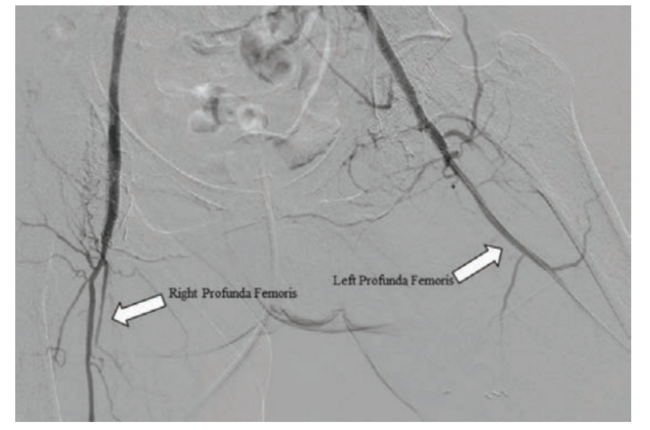

A 59-year-old woman presented with a history of bilateral above-knee-amputations, prior right-sided common iliac, external iliac, and common femoral arterial stenting, coronary artery disease with coronary arterial stenting, chronic obstructive pulmonary disease, hypertension, hyperlipidemia, diabetes mellitus (Type II), and tobacco dependence. The patient’s bilateral ischemic rest pain was not well controlled on oxycodone, gabapentin, and cilostazol. The ischemic rest pain, even with opioid therapy, prevented the patient from wearing her prostheses. Prior failed attempts to gain access to the bilateral occluded common femoral arteries left the patient with no obvious options for revascularization. After review of previous imaging, left brachial access was deemed most appropriate for a revascularization attempt. An OmniFlush catheter (AngioDynamics) was positioned at the level of the distal aorta for an abdominal aortography with runoff (Figures 1 and 2).

The angiogram demonstrated total occlusion of the right common iliac, external iliac, and common femoral stents. The right superficial artery had a flush ostial occlusion with no appreciable flow. Collateral flow filled in the right profunda femoris, which then provided collaterals to the stump. The left common iliac had appreciable flow, but flow became severely diminished at the start of the left external iliac artery. The left internal iliac fed the left profunda femoris through collateral flow. The left common femoral and left superficial femoral arteries were occluded, mirroring the right lower extremity.

Next, we focused on the left common femoral artery. A Victory 14 guidewire was used to cross the left common femoral artery; however, the wire kept entering the subintimal plane. A dual arterial access approach was adapted to cross the CTO of the left common femoral artery. Retrograde access was achieved in the left profunda femoris, placing a short 4 French Micropunture pedal sheath (Cook Medical) into the left profunda femoris. A .014-inch Astato XS40 (Asahi Intecc) was advanced through a CXI support catheter (Cook Medical) from the retrograde sheath. The .014-inch Astato XS 40 extended proximally. However, the wire continued to cross the subintimal plane. A 3 mm × 80 mm Advanced Micro balloon (Cook Medical) was advanced from the retrograde sheath and was approximated with a 5 mm × 200 mm Armada PTA balloon from the antegrade sheath. A double balloon angioplasty technique was performed such that the antegrade lumen became fenestrated with the retrograde lumen. This allowed the V-18 ControlWire guidewire (Boston Scientific) to be externalized from left brachial access through the 4F micropunture pedal sheath. The 5 mm × 200 mm Armada PTA balloon was advanced across the left common femoral into the profunda femoris. A balloon angioplasty was performed that adequately prepared the arterial vasculature for an Innova self-expanding stent (Boston Scientific) in the left common femoral artery and a Zilver 518 Vascular self-expanding Stent (Cook Medical) in the left external iliac artery, taking the heavily diseased segments to 10% residual stenosis (Figure 3). This intervention provided direct inline flow to the left profunda femoris, which then provided collateral flow to the left lower extremity stump (Figure 4).